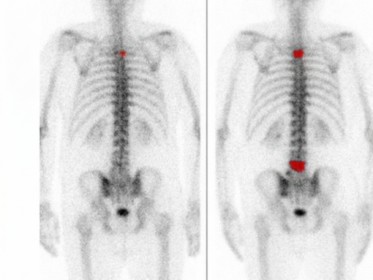

La comprensione della malattia di Alzheimer (AD) ha subito un’evoluzione paradigmatica negli ultimi decenni, passando da una diagnosi basata esclusivamente sull’osservazione clinica ex post a una caratterizzazione biologica in vivo supportata da biomarcatori avanzati. In questo contesto, la Tomografia ad Emissione di Positroni (PET) con il radiofarmaco 18F-fluorodeossiglucosio (18F-FDG) si è affermata come uno strumento…